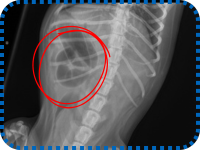

X-rays confirmed everyone’s fears: the sock was stuck. Ozzy couldn’t pass it, and he urgently needed help. Because of supporters like you, that help was ready.

Ozzy went straight into surgery, and it was then our veterinary team discovered the sock had caused serious damage. A portion of Ozzy’s intestine had to be removed, and there was a very real danger that his small body might not recover.